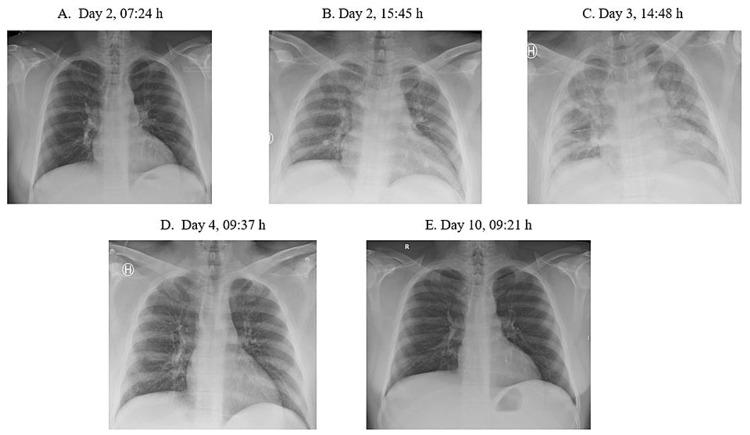

Acute chest syndrome (ACS) is a severe form of vaso-occlusive crisis, which is a main feature of sickle cell disease (SCD), an inherited hemoglobinopathy. Traditionally, hydroxyurea has been the treatment of choice for SCD to prevent vaso-occlusive crises including ACS. However, hydroxyurea may be contraindicated, for example, in patients wanting to have children. We here present a young male with SCD who wanted to become a father and developed a life-threatening episode of ACS following discontinuation of hydroxyurea and switching to partial exchange blood transfusions. The patient, aged 32 years and originally from Bahrain, had been diagnosed with homozygous SCD, alpha-thalassemia, and glucose-6-phosphate dehydrogenase deficiency as a child. He had an episode of ACS with moderate severity in 2008, after which he started using hydroxyurea. From 2008 until the present, he did not experience any episodes of ACS. About six months before the present episode, he stopped using hydroxyurea and switched to partial exchange transfusions, aiming to keep hemoglobin S (HbS) below 30%. The interval between the transfusions was typically about seven to eight weeks. On the evening (day 1) before hospital admission, he developed typical symptoms and signs of vaso-occlusive crisis, and during the first day in the hospital (HbS about 55%), his pulmonary function deteriorated, and he also developed cerebral symptoms (somnolence and confusion). On suspicion of ACS, a full blood exchange transfusion was administered on day 3. He then gradually recovered clinically, and his laboratory values also normalized. He was discharged on day 10. Subsequent follow-up visits at the outpatient clinic the following month were unremarkable. Possibly, this severe episode of ACS was triggered by switching from hydroxyurea therapy to partial exchange transfusions with too long intervals between the transfusions. This novel case is a compelling reminder of the possible perils that may accompany the discontinuation of hydroxyurea, the best-documented therapy in SCD.